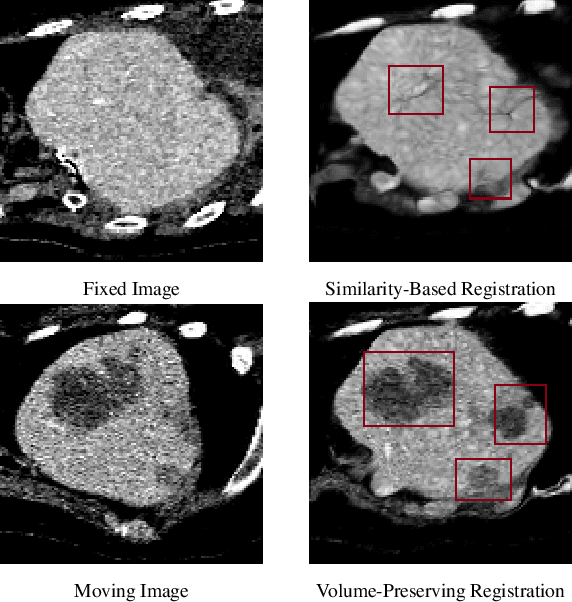

Abstract:Medical image registration is a critical task that estimates the spatial correspondence between pairs of images. However, current traditional and deep-learning-based methods rely on similarity measures to generate a deforming field, which often results in disproportionate volume changes in dissimilar regions, especially in tumor regions. These changes can significantly alter the tumor size and underlying anatomy, which limits the practical use of image registration in clinical diagnosis. To address this issue, we have formulated image registration with tumors as a constraint problem that preserves tumor volumes while maximizing image similarity in other normal regions. Our proposed strategy involves a two-stage process. In the first stage, we use similarity-based registration to identify potential tumor regions by their volume change, generating a soft tumor mask accordingly. In the second stage, we propose a volume-preserving registration with a novel adaptive volume-preserving loss that penalizes the change in size adaptively based on the masks calculated from the previous stage. Our approach balances image similarity and volume preservation in different regions, i.e., normal and tumor regions, by using soft tumor masks to adjust the imposition of volume-preserving loss on each one. This ensures that the tumor volume is preserved during the registration process. We have evaluated our strategy on various datasets and network architectures, demonstrating that our method successfully preserves the tumor volume while achieving comparable registration results with state-of-the-art methods. Our codes is available at: \url{https://dddraxxx.github.io/Volume-Preserving-Registration/}.